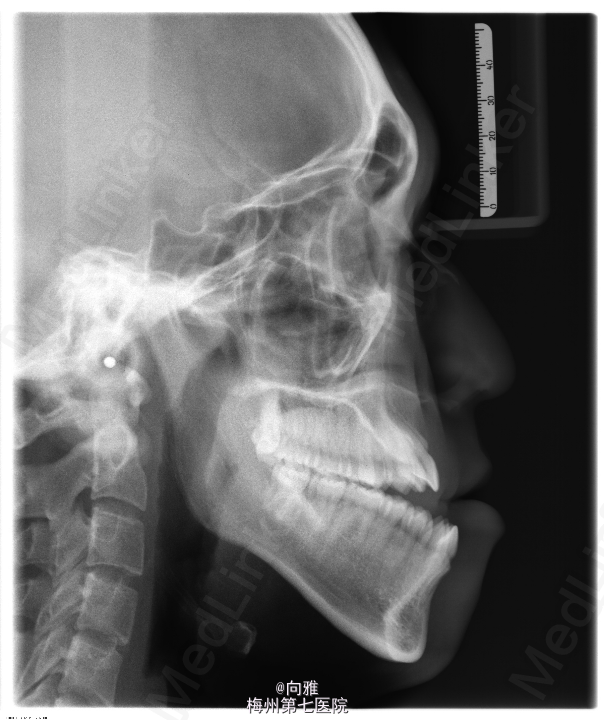

青年男患者,下颌前突十余年,患者于十年余前无明显诱因出现上颌后缩,下颌前突,影响美观及咬合,逐渐加重,未行处理,1年前于我院正畸科就诊,制定“正畸-正颌联合”治疗方案,遂行正畸治疗,现已完善术前正畸,今为行正颌手术入院治疗

双侧颌面部基本对称,侧面观:面下1/3前突。左侧颞下颌关节触及弹响,右侧颞下颌关节未触及弹响,双侧颞下颌关节无压痛。开口型“↓”,开口度3.5cm。口内全口牙列正畸托槽,前牙开合、反合,约2cm,双侧后牙I类关系。

1.下颌前突 2.偏颌畸形,全麻下行BSSRO后退术+双侧下颌骨去骨皮质术+坚固内固定术